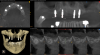

CBCT evaluation indicated that all four implants were healthy, and a decision was made to place two more implants. The plan called for one implant to be placed on each side to create an all-on-six solution. In the maxillary right quadrant, an implant would be placed between the two existing implants. The complexity of maintaining 3 mm of adequate space between each implant in the right quadrant for hygiene maintenance and adequate blood supply necessitated the use of guided surgery, as failure to maintain the 3 mm inter-implant spacing can result in severe bone loss and peri-implantitis.19In the left quadrant an implant was planned posterior to the most distal implant, thus requiring the implementation of the OD sinus lift protocol described in Case 1 (Figure 10).

Fig 10. CBCT revealed relatively non-complex implant placement on

the maxillary right side for the maintenance of 3 mm between each

implant and less than 6 mm residual bone height on the maxillary left

side.

Fig 12. CBCT of final implant placement with

cross-section of maxillary left side sinus elevation.

Figure 12